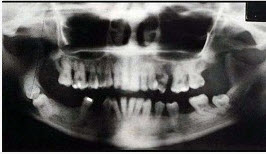

关于快速进展性牙周炎,哪项正确()。